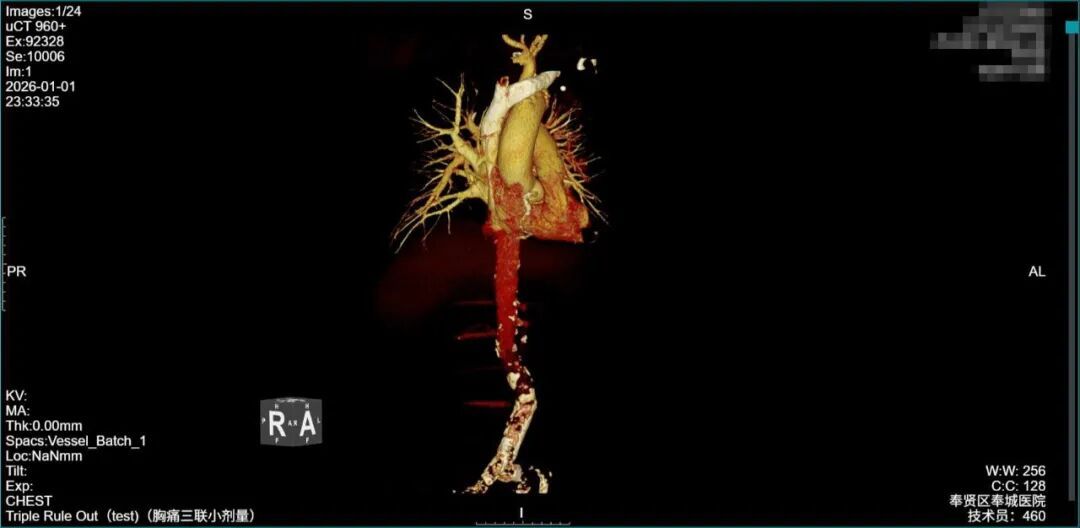

“必须第一时间保命!”团队一边争分夺秒讨论方案,一边紧急联系上海市第九人民医院血管外科陆信武教授。远程+现场双重研判后,专家团队敲定了一套“个体化微创方案”:先通过“胸主动脉腔内修复术(TEVAR)+激光原位开窗+左侧锁骨上动脉支架植入术”堵住破口、重建血管,等患者情况稳定后,再择期进行“胸腔血肿清除引流”。这套方案最大限度减少手术创伤。

数字减影血管造影(DSA)的屏幕上,每一个操作都关乎生死。医生如同“血管里的拆弹专家”,在毫米级空间内操控器械,将覆膜支架稳稳输送至破裂处——“释放!”随着一声指令,支架瞬间展开,精准“堵”住主动脉破口,出血立即得到了有效控制!紧接着,团队再经左侧肱动脉穿刺,通过激光原位开窗技术为左侧锁骨上动脉“开辟通路”,成功完成血管重建。

术后影像显示:覆膜支架定位精准,主动脉破口被完全隔绝,血管血流恢复正常!